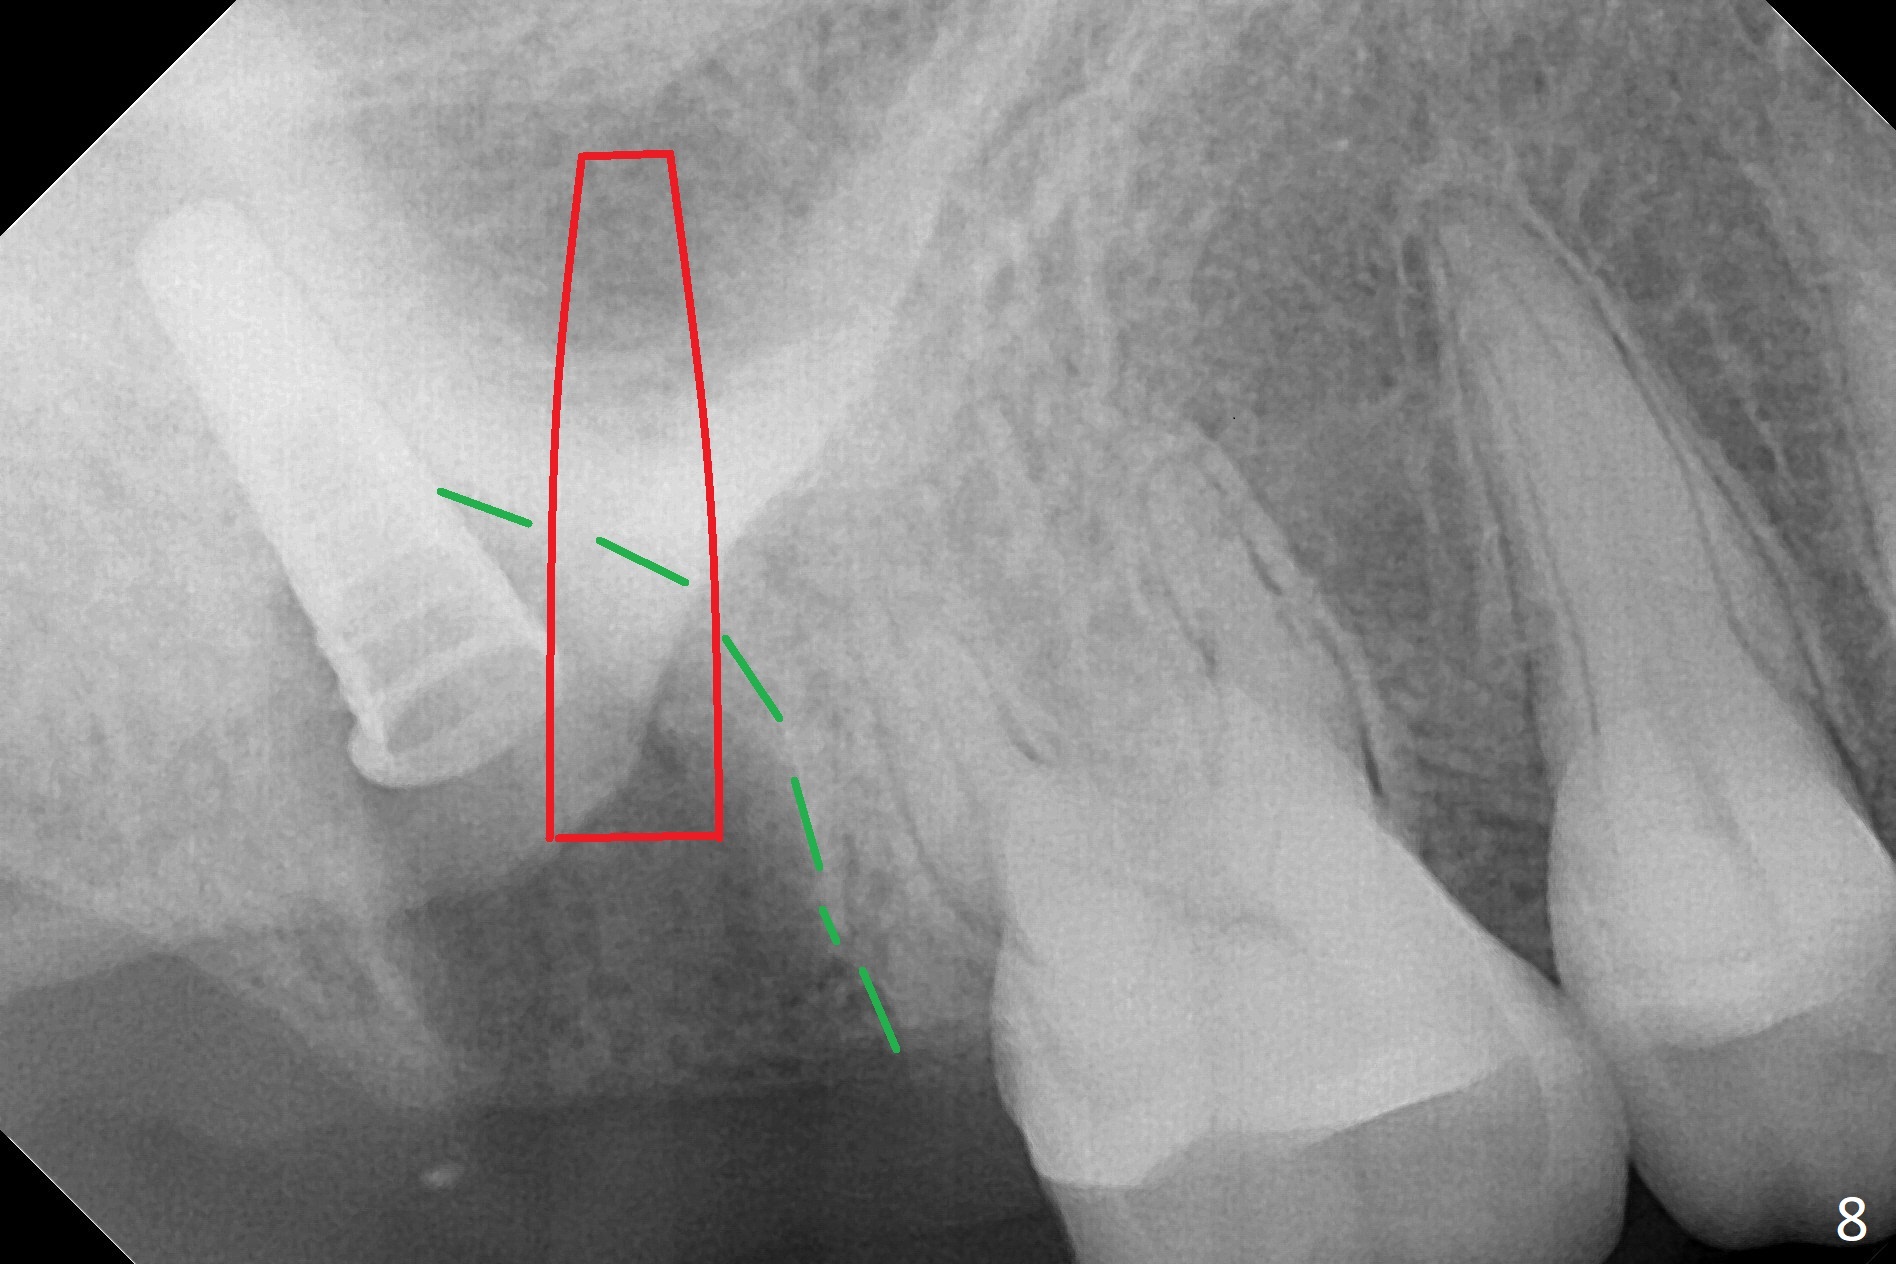

Fig.5 shows the mesial slope of the socket (M), which is more or less the center of the socket mesiodistally. If the osteotomy were set up in the red circle (Fig.6) in the mesial slope (Fig.8 green dashed line), the trajectory of 4.5x11 mm dummy implant (Fig.7) would be more ideal (Fig.8 red outline) with more native bone contact. Finally a longer IBS implant is placed (4.5x15 mm, Fig.9,10) to achieve primary stability (50 Ncm). When the provisional is removed for impression 3 months 10 days postop, the implant is found to have been placed distopalatally (Fig.13), which should have been avoided. It appears essential to use guide for a distal implant. It is agonizing to re-encounter the off-axial implant (Fig.14) and the distopalatal access hole (Fig.15) 1 year post cementation. It is also amazing that the abutment screw has not loosened. A fair-sized piece of bone graft has just been removed buccally (Fig.15,16). The patient complains of sensitivity 2 years 3 months post cementation, although there is no abnormality around the implant crown. Guided surgery is essential to avoid restoration complication. There is no thread exposure nearly 3 years post cementation; in fact the apical portion of the abutment is covered by the bone (Fig.17,18).